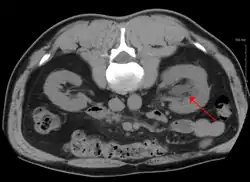

CT scan of bilateral hydronephrosis due to a bladder cancer CT scan of bilateral hydronephrosis due to a bladder cancer

Stone causing hydronephrosis[16]